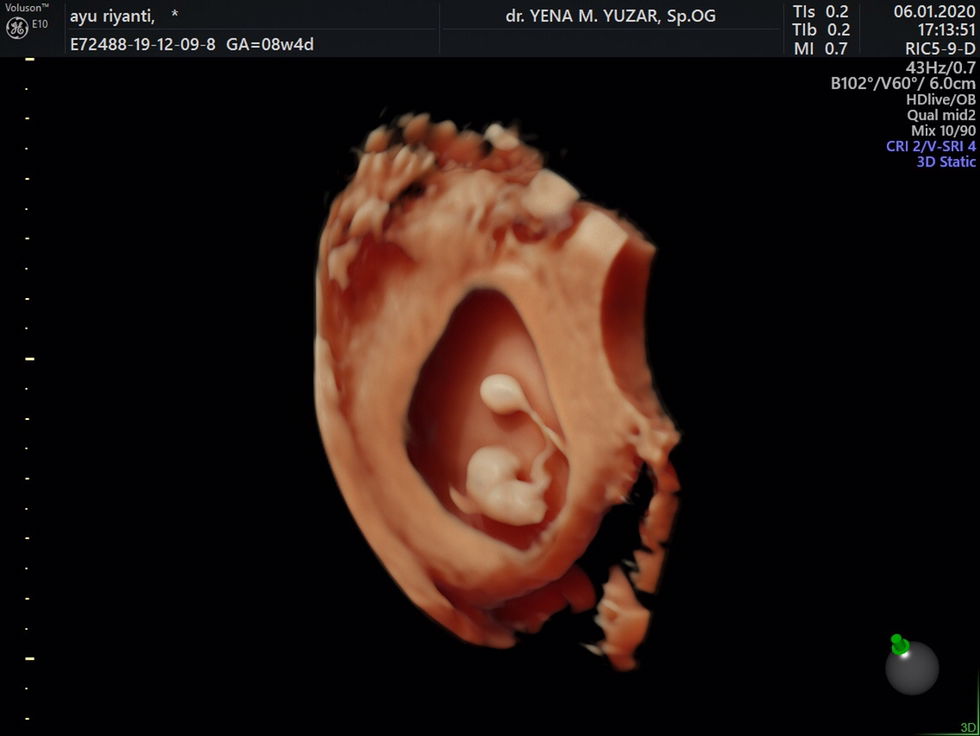

Hamil 8w4d